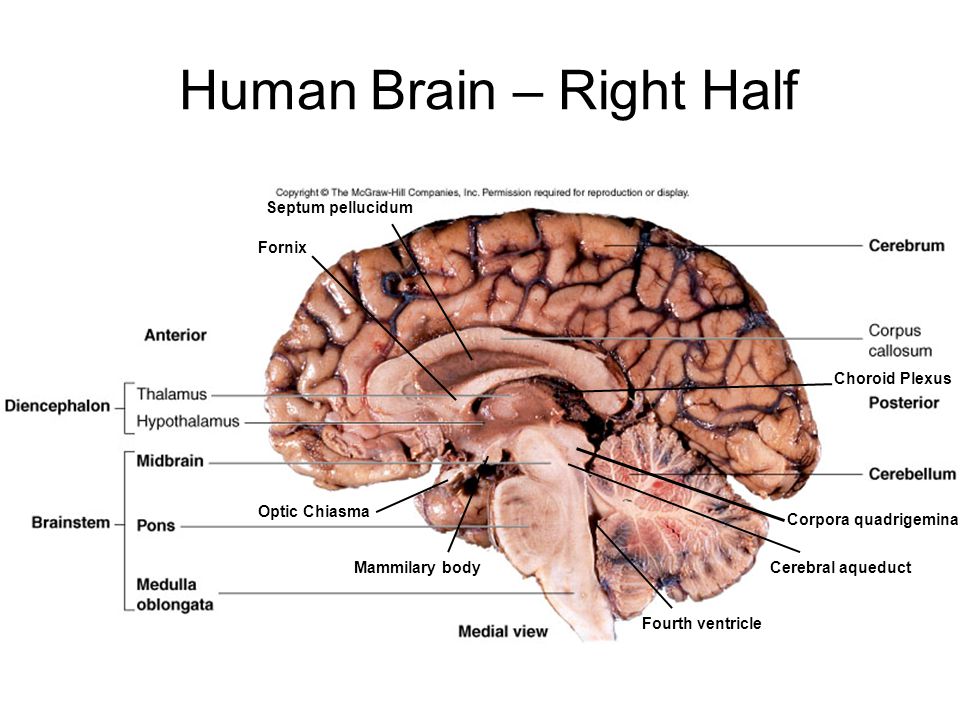

Анатомические снимки верхнелатеральной поверхности головного мозга